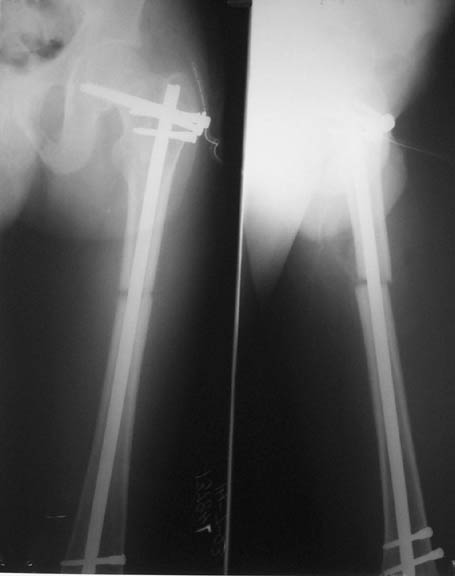

We managed to get neutral phosphate, initiated medical treatment and did an antegrade SIGN nailing of left femur along with couple of screws to neck using miss a nail technique. He complained of pain of the right femur and both forearms. In OT these areas were screened using image intensifier and found that he has looser zones of all these with impending fractures. Yesterday we did a retrograde nailing of right femur usingSIGN nail. Both ulnas were stabilised usingLambrudini wires in a closed fashion. All fractures and looser zones were stabilised by closed surgery using image intensifier. It may be interesting to see the post of picture of both the hips in which one side shows an antegrade femoral SIGN nail and the other side shows a retrograde SIGN nail.